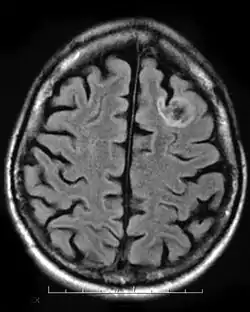

Tumeur neuroépithéliale dysembryoplasique (TNT)

Une tumeur neuroépithéliale dysembryoplasique est une tumeur bénigne rare qui touche les enfants et les adolescents de moins de vingt ans. La tumeur se produit dans le tissu recouvrant le cerveau et la moelle épinière. Les symptômes de la tumeur dépendent de sa localisation, mais la plupart des enfants souffrent de crises qui ne peuvent être contrôlées par des médicaments. Elle est généralement traité par chirurgie invasive et les patients sont généralement capables de récupérer complètement, avec peu ou pas d'effets à long terme[9].